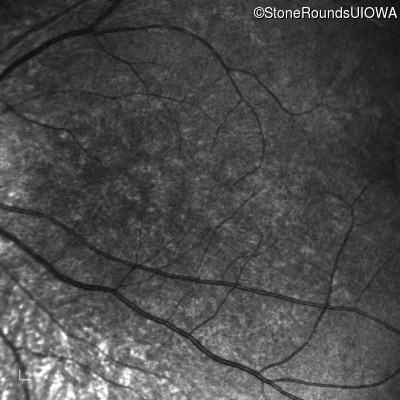

Infrared Fundus Photograph - Right - 5/200

Exemplar